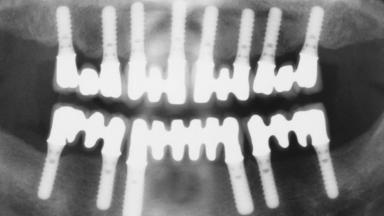

Immediate Loading of Eight Implants in the Maxilla and Six Implants in the Mandible and Final Restoration with Three-Unit and Four-Unit FDPs

Extensive scientific evidence has confirmed that immediately loaded implants with fixed full-arch provisional restorations can osseointegrate with success rates similar to conventionally or delayed loaded implants. A number of immediate-provisionalization techniques for edentulous jaws have been described. Some protocols differ when it comes to prefabricated provisional templates versus complete denture conversion; intrasurgical impressions versus direct relining; and cemented versus screw-retained provisional restorations. In this context, complete-denture conversion has been proposed for either intrasurgical impressions or direct relining. Another possibility is the utilization of a prefabricated provisional to be adapted either in the mouth (by direct relining) or in the laboratory (on a working model obtained from an intrasurgical impression).